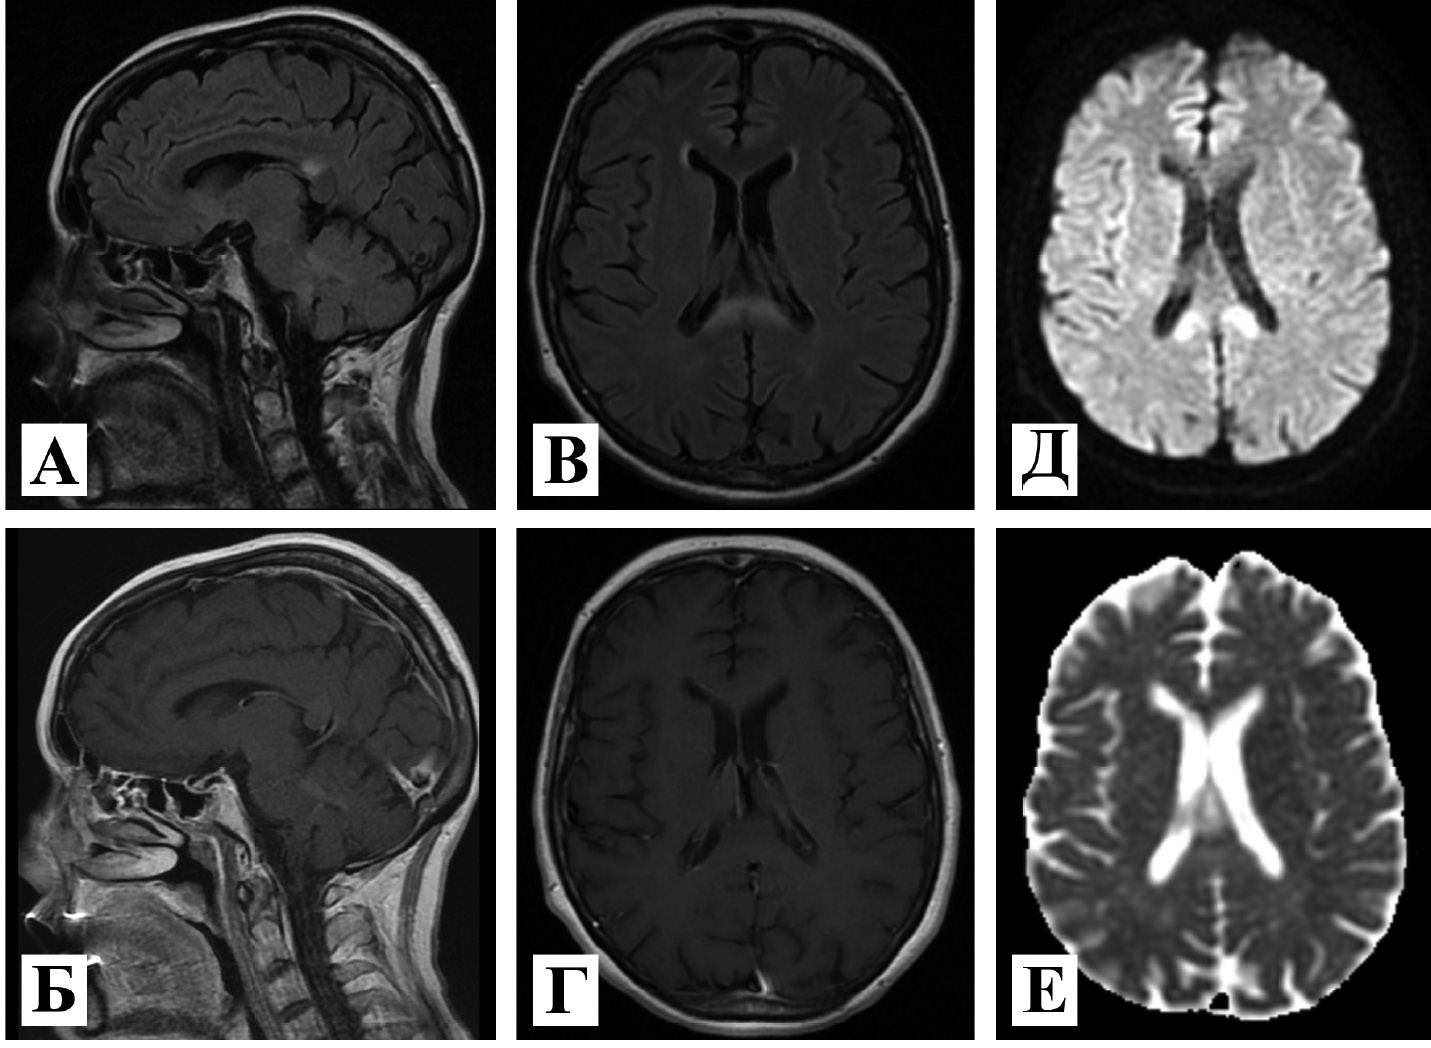

2. Рис. 2. МРТ головного мозга с контрастным усилением, 1,5 Тл. Сагиттальная проекция в режимах: А – Т2-FLAIR; Б – Т1 с контрастным усилением. Аксиальная проекция в режимах; В – Т2-FLAIR; Г – Т1 с контрастным усилением; Д – DWI; Е – ADC. Отмечается зона патологического МР-сигнала в валике мозолистого тела с нечеткими контурами, характеризующаяся частично неоднородным гиперинтенсивным МР-сигналом на Т2-FLAIR, слабо гипо- и изоинтенсивным на Т1 ВИ. При выполнении DWI с b = 1000 отмечается преобладание вазогенного отека с наличием линейной формы участка цитотоксического отека. | |